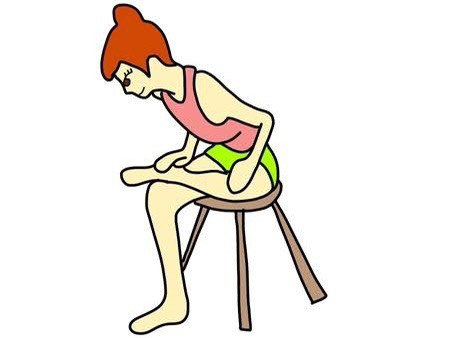

1臀部のストレッチ (目安は30秒を3〜5セット)最初は10秒ほどでも良い

痛みが出る場合は無理に行わず優しくゆっくり時間をかけて行うか、原因が違うこともありますのでやらない方がいい場合もありますのでご自分の体に合わせて行ってください。